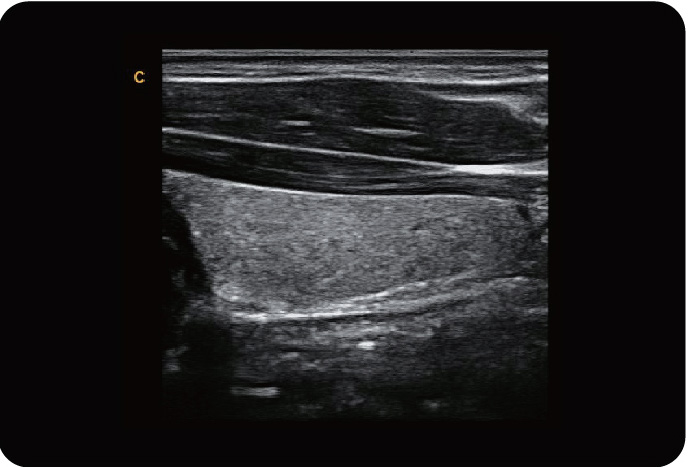

脐动脉,C模式

颈动脉,C模式

甲状腺,C模式

甲状腺,B模式